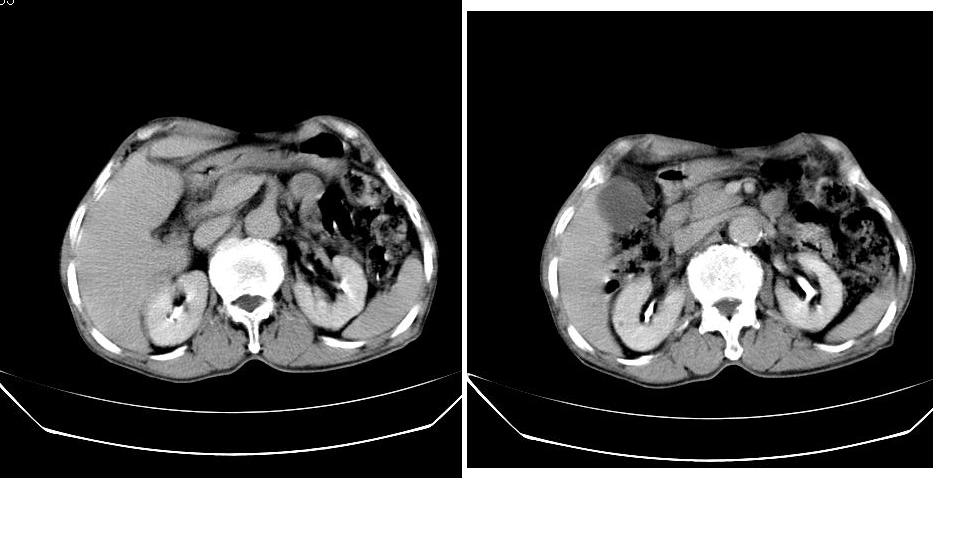

男,76岁,上腹部疼二天来就诊,彩超提示肝左叶占位,随后做上腹部ct平扫,今天做上腹部ct增强扫描,手工推药,效果不好,请谅解。

肝左叶s4肿块强化形式大概是:慢进慢出,逐渐强化----考虑血管瘤/腺瘤?{动脉期应更提前扫}。

肝右叶前段hcc

1)肝右叶前段低密度灶,不排除肝癌可能;建议查afp。2)右肾上极囊肿。

肝内胆管积气扩张,胆囊增大,肝右前叶低密度灶,逐渐强化,一元论,胆系感染,局限性肝脓肿;右肾囊肿。

考虑肝s4段肝脓肿可能?未排除肝癌。右肾上极囊肿。